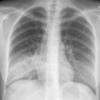

Case 2 Lingular pneum PA

Date: 04/17/2005

Views: 6409